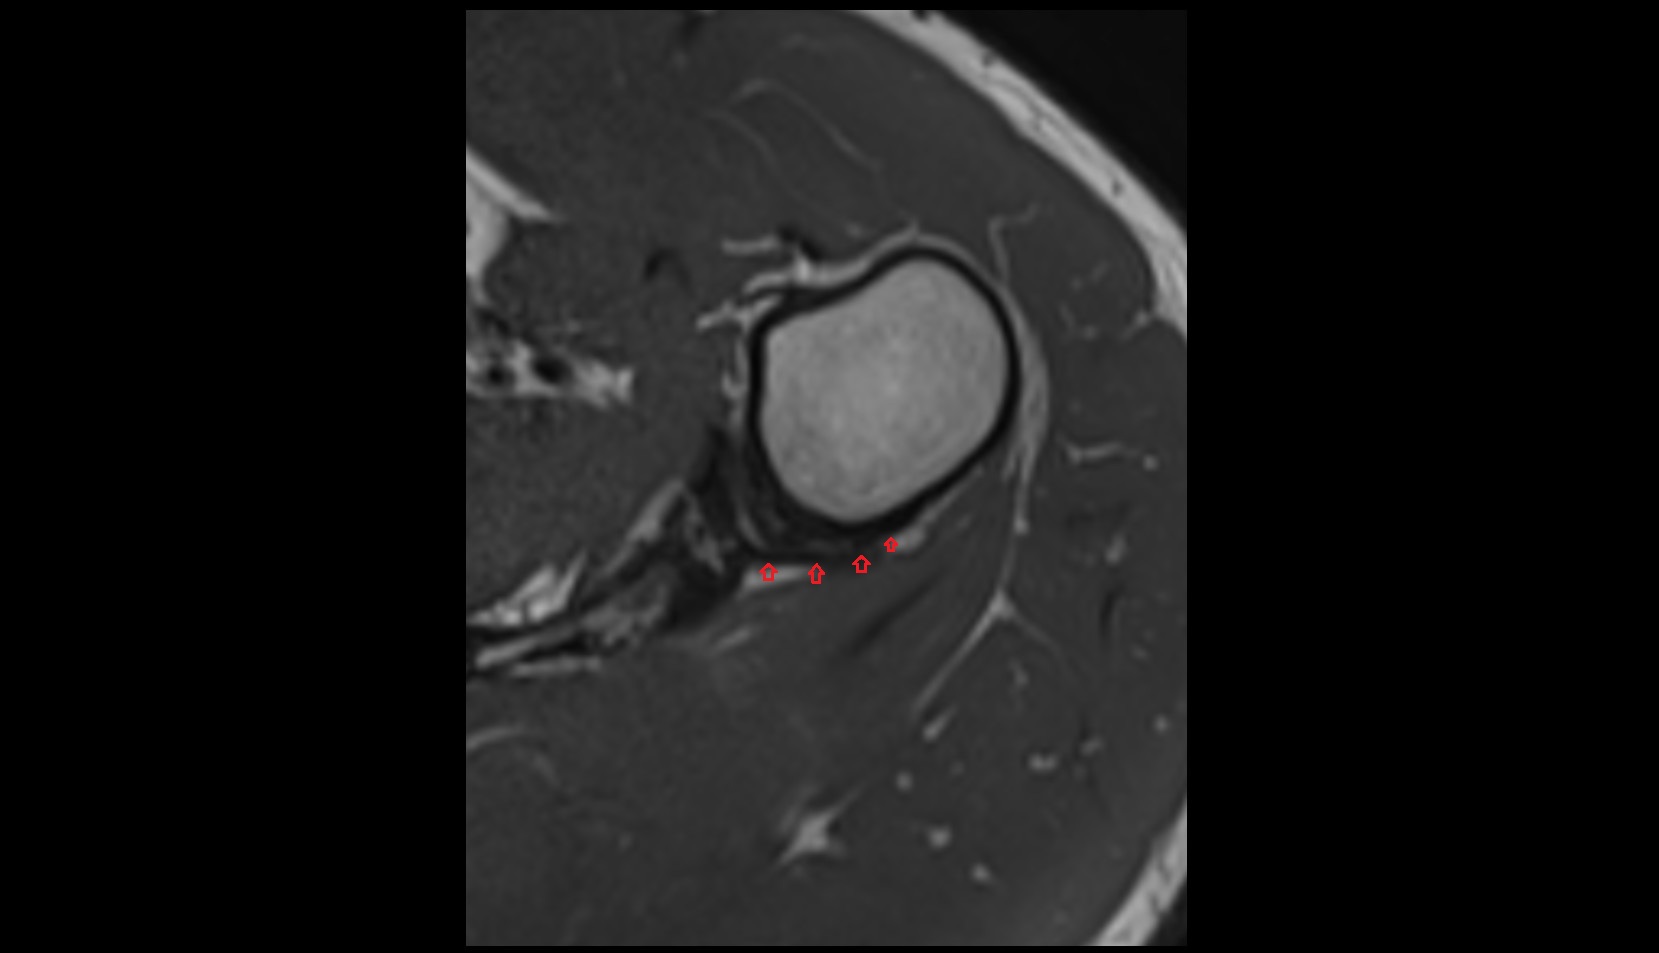

- Glenoid labrum

- Shoulder joint (glenohumeral joint)

- Glenohumeral joint capsule

- Supraspinatus tendon

- Infraspinatus tendon

- Subscapularis tendon